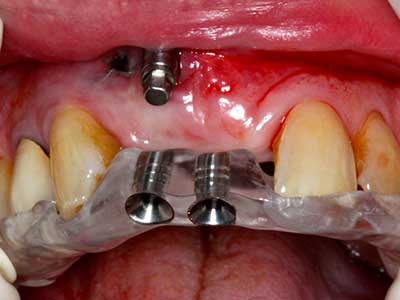

Fig. 8: dopo il rialzo del seno, il supporto per l'osso crestale viene fissato alla cresta alveolare con difetto.

Fig. 9: membrana interna con materiale di riempimento costituito da osso bovino (Cerabone 0,5–1 mm, Botiss biomaterials, Berlino) e osso autologo (vista palatale).

Fig. 10: copertura della regione dell'accrescimento con una membrana pericardica a lunga durata fissa (membrana in collagene Jason, Botiss).